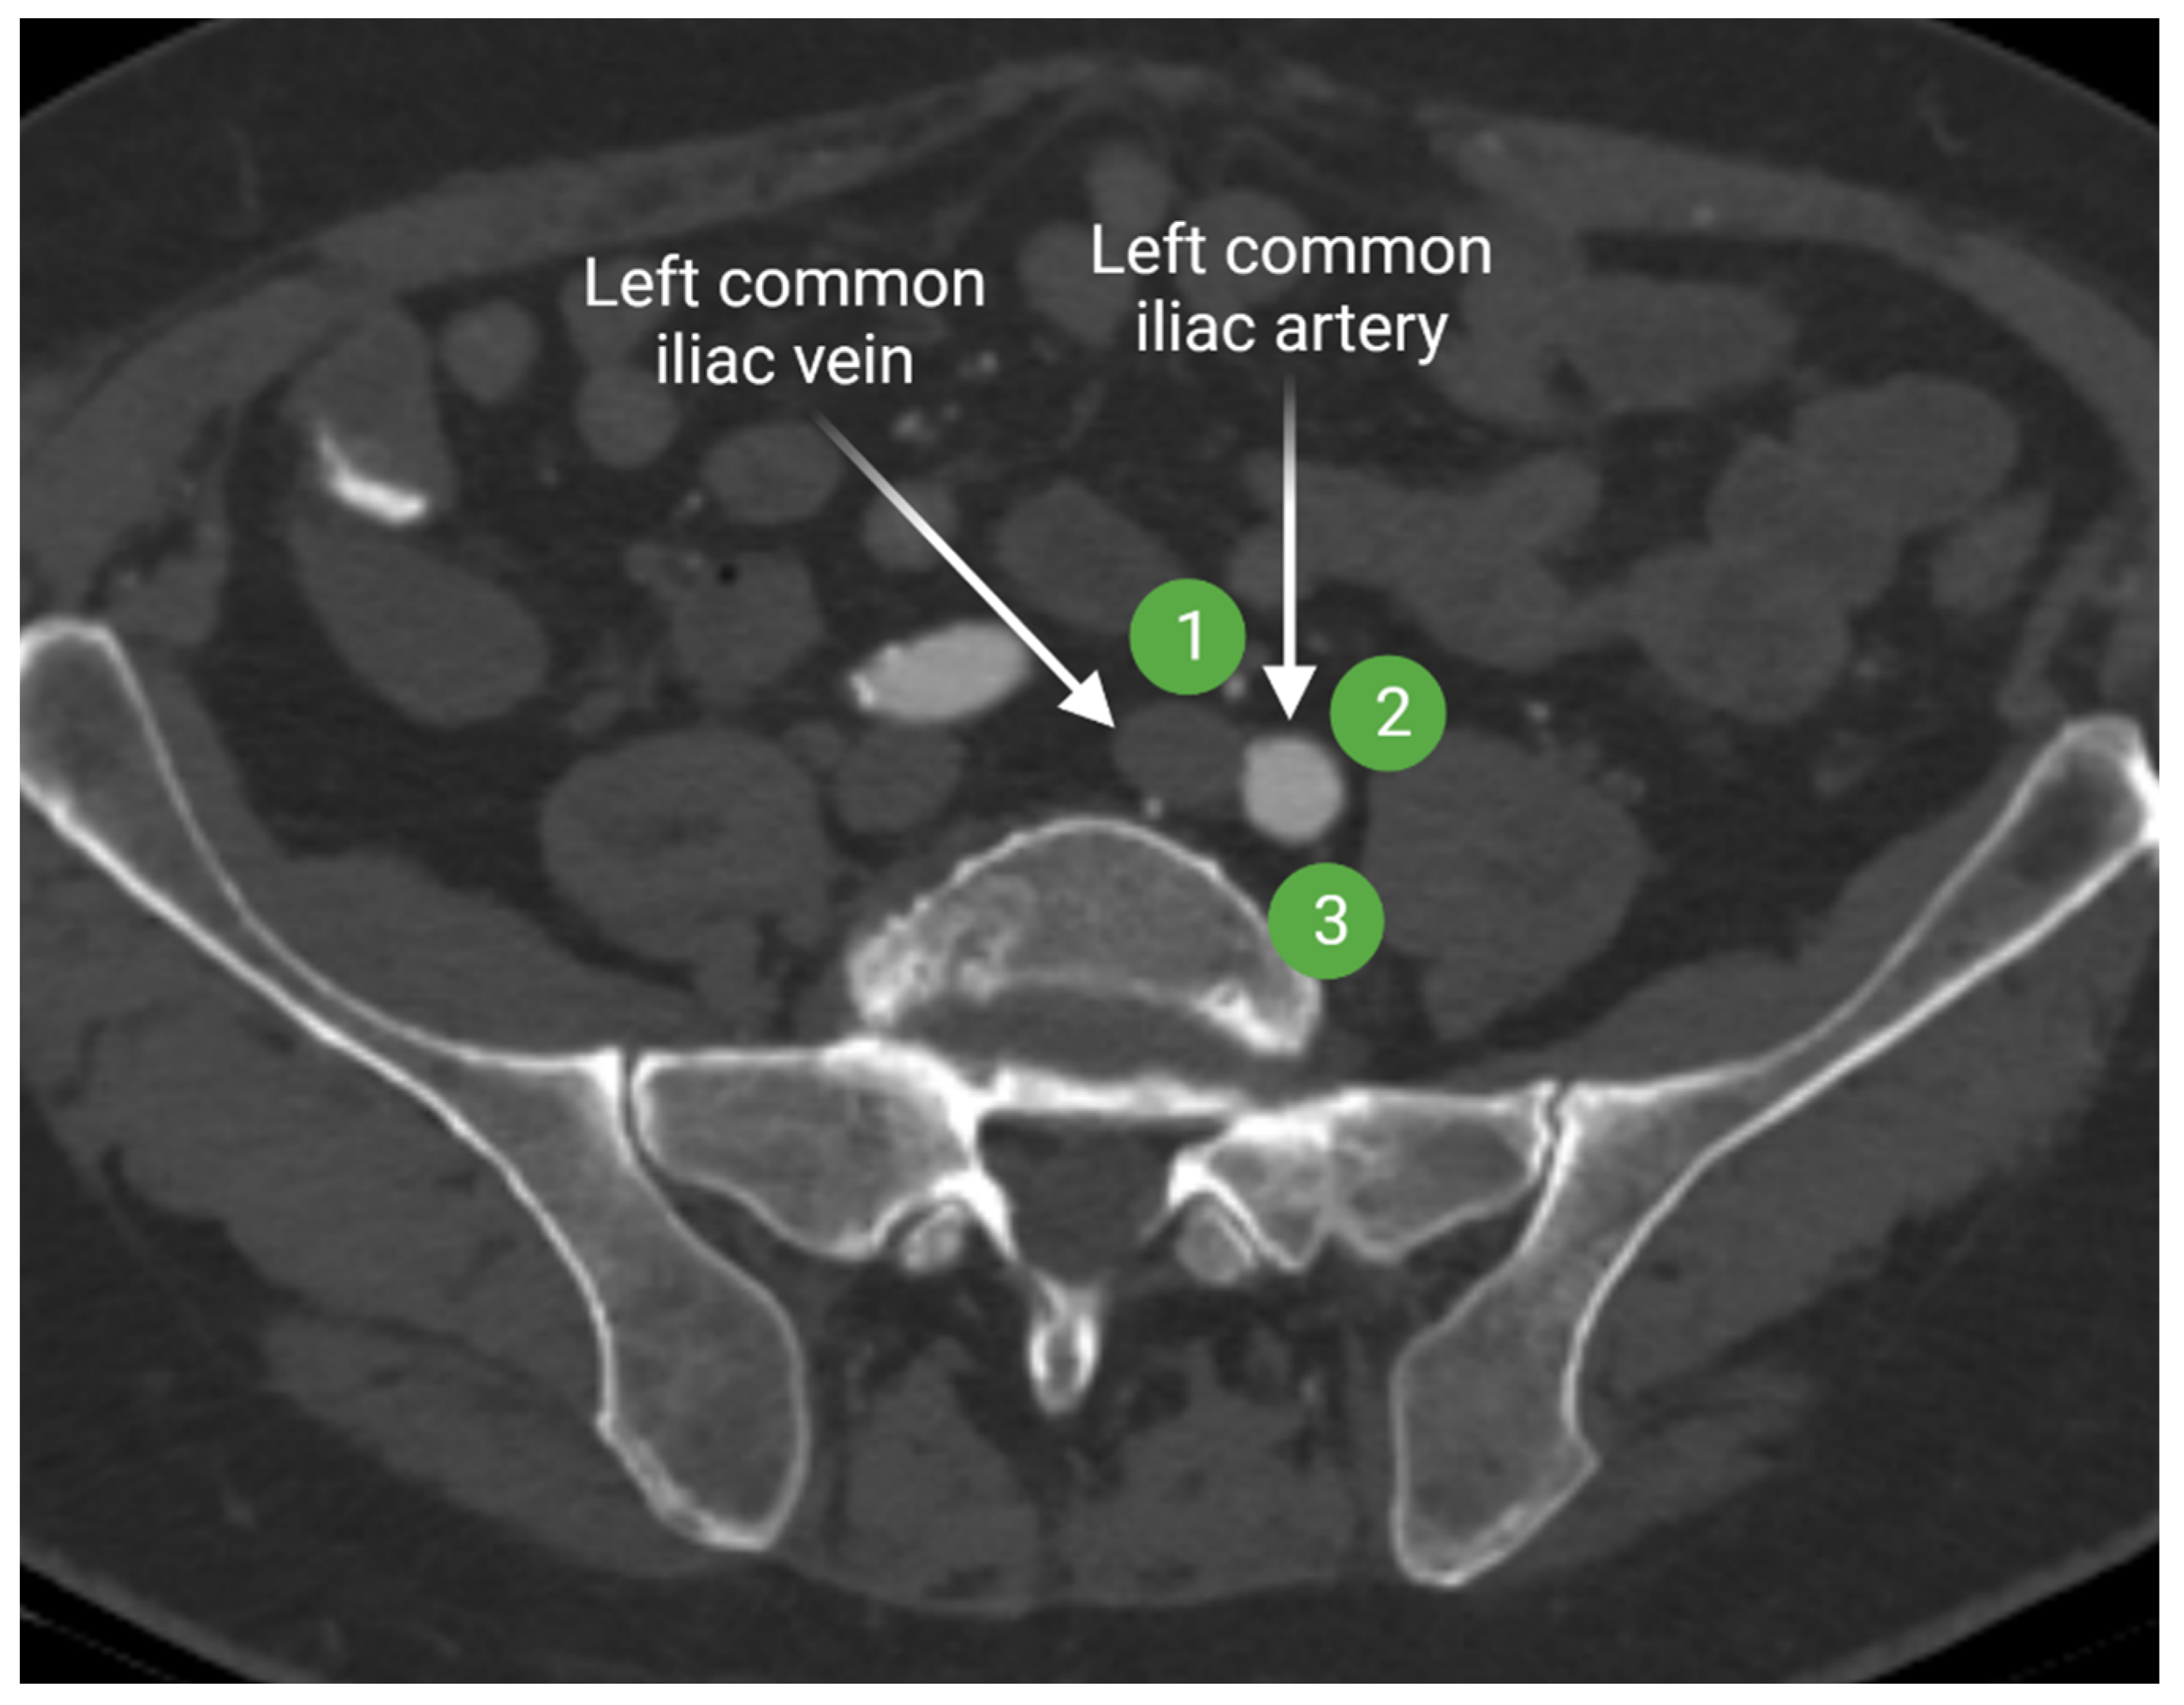

2.1.2. Iliac Lymph Nodes Anatomy